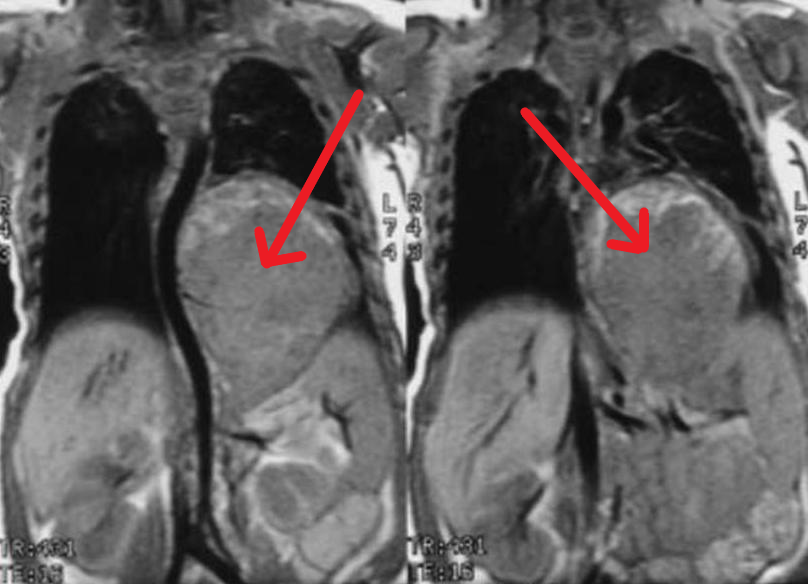

Нейробластома - высокозлокачественная опухоль симпатической нервной системы, которая практически встречается исключительно у детей. Опухоль может развиваться везде, где есть симпатические клетки вегетативной нервной системы, но в подавляющем большинстве располагается в одном из надпочечников.

Подозрение на нейробластому возникает, когда обнаруживается увеличение размеров живота, а при пальпации выявляется плотная, практически несмещаемая опухоль.